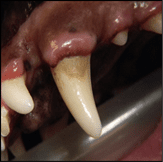

- Canine acanthomatous ameloblastoma (CAA): This is a slow-growing, expansile tumor that occurs most commonly in medium to large breed dogs. Canine acanthomatous ameloblastoma is not considered malignant, BUT it is locally invasive and includes gingiva, oral mucosa, and bone. Surgical removal involves the removal of ALL the tumor, including where it is detected in the jawbone. Canine acanthomatous ameloblastoma is often found at the front of the mouth, affecting the incisor or canine teeth.

CAA causing tooth displacement of the mandibular incisors

CAA appearance affecting the lower jaw (mandible)